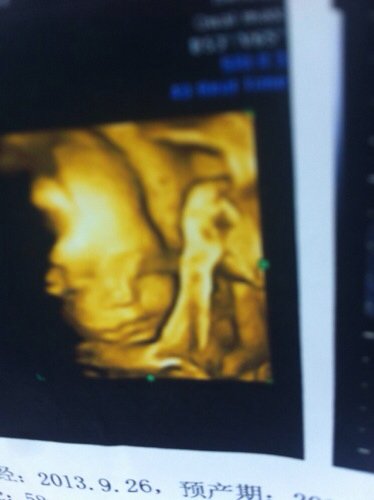

这是24周做的四维彩超图,帮忙看下图片有问题吗?我怎么感觉鼻子和眼睛怪怪的,好担心 点击展开 匿名用户 2014-04-08 08:58 为您推荐: 其他回答 病情分析: 你好,其并不能说明胎儿发育异常的。 指导意见: 保证充足的能量,增加鱼,肉,蛋,奶的摄入.注意做好孕检即可. 独水凡_xjeq 2014-04-08 10:13 相关问题 这个是二十四周做的四维彩超图,感觉鼻子和眼睛有问题,大家帮忙看下? 我怀孕24周了鼻子一投就躺血这是为什么 24周了,吃补眼的对宝宝的眼睛发育还有用吗?